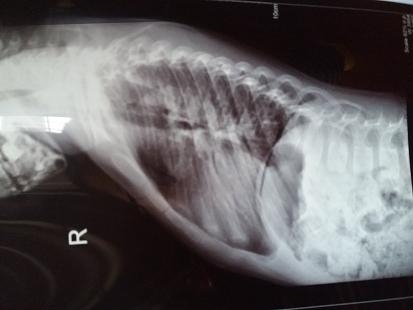

小孩术后5年,最近久咳不止。胸片显示心影增大成球形,心胸比约0.61。

彩超报告: 2016年心脏彩超结果为:1、右心增大;2、三尖瓣返流轻度;3、肺动脉版返流轻中度。

从胸片上看,心脏还是偏大了一些,建议还是继续随访复查吧。